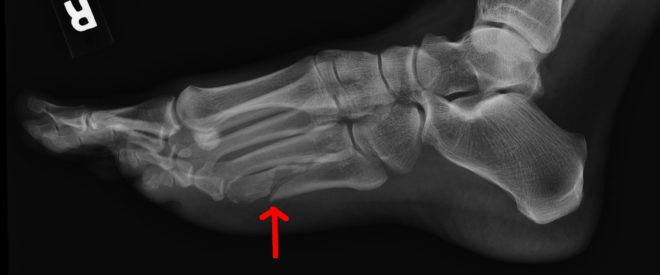

Ключевыми симптомами маршевой стопы являются легкие боли и отечность в пораженной области. Рентгеновский снимок в остром периоде заболевания показывает характерные участки переломов. Повреждение костей происходит по принципу зеленой ветки: ломаются только глубокие слои костной ткани, в то время как поверхностные остаются нетронутыми. Эти особенности можно подробно рассмотреть на фотографиях.

Свежие переломы можно выявить с помощью магнитно-резонансной томографии. Рентгенолог, используя специальные техники, может заметить снижение плотности тканей, что свидетельствует о трещинах в плюсневой кости. Такие переломы, как правило, не требуют вправления.